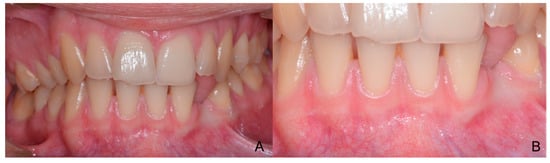

1.1. Case Number 1